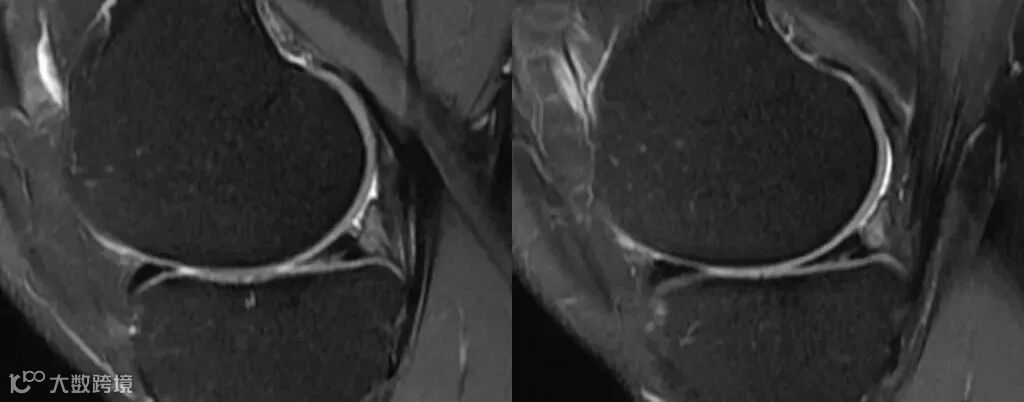

骨关节成像用高带宽 -

如在评估关节软骨及细微结构时,需要关注的重点则是如何保留更丰富的对比信息,减少模糊伪影,则建议使用高带宽来减小回波间隙,以达到改善模糊效应保证细节对比的目的。